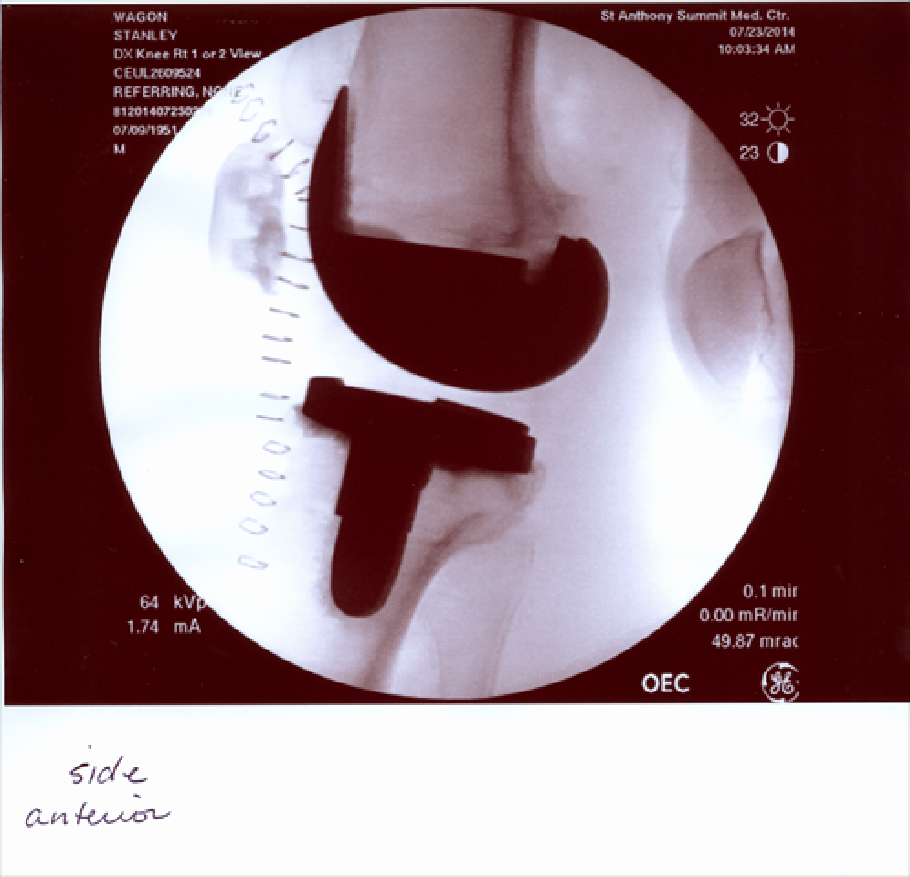

Here is the view from front to back. The space between the implants is occupied by plastic (polyethylene), which takes the place of cartilage. This is the spacing that a good knee shows, and which I did not have. The staples are on the inside (medial) of the leg.

And this is the side view, anterior to medial. Kneecap at left. Bone at right is the other leg. Patella at upper left. Fibula is visible, but the knee connects femur with tibia. There is more to the implant than one can see. Posts fix the pieces in place, and make the removed ACL and one other ligament irrelevant for stability. And a plastic piece is attached to the inside of the patella.